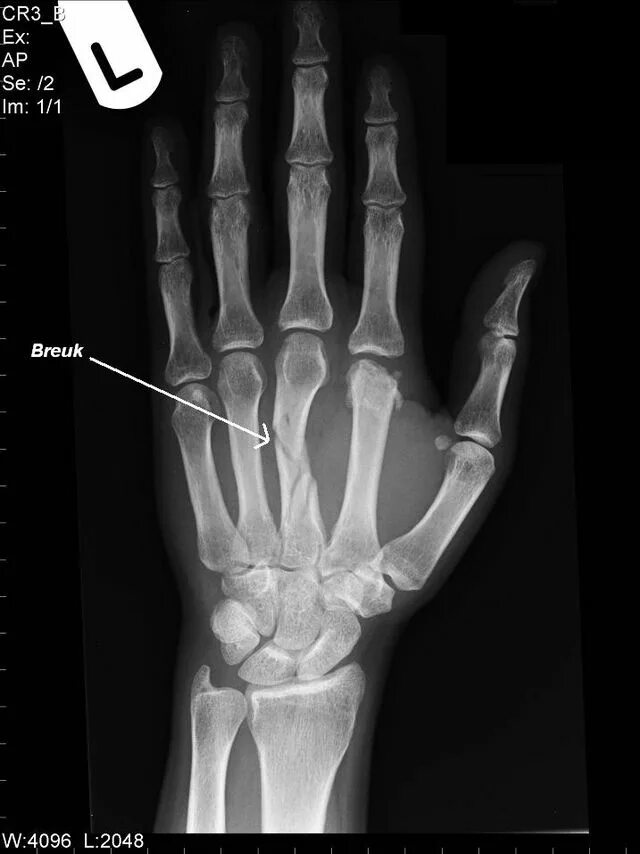

Перелом 3 пястной кости